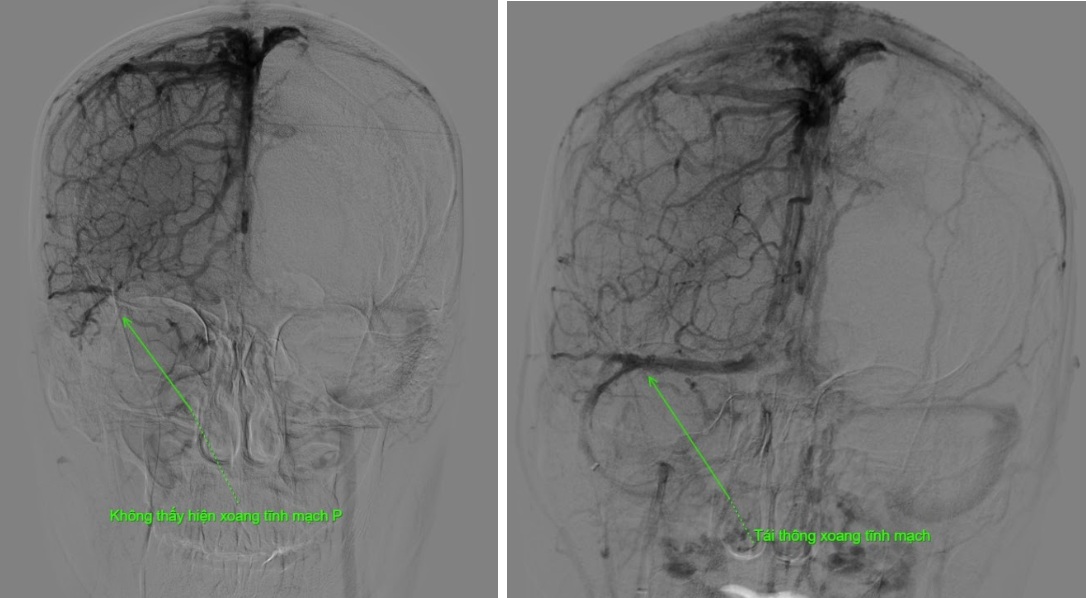

Kết quả phim chụp cho thấy bệnh nhân bị tắc gần như toàn bộ hệ thống tĩnh mạch dẫn lưu não, bao gồm xoang dọc trên, xoang ngang, xoang sigma và đoạn đầu xoang tĩnh mạch cảnh trong phải.

“Không giống như huyết khối động mạch, để lấy huyết khối tĩnh mạch não chúng tôi phải tiếp cận qua đường tĩnh mạch. Trước tiên, ê-kíp tiến hành chụp động mạch não để hiện hình hệ thống xoang tĩnh mạch và xác định vị trí huyết khối trên máy DSA. Sau đó, hệ thống dụng cụ được đưa từ tĩnh mạch đùi lên tĩnh mạch cảnh trong phải để lấy huyết khối từ tĩnh mạch cảnh trong lên đến xoang dọc trên - vị trí có huyết khối. Từ đây, chúng tôi lấy toàn bộ huyết khối từ xoang dọc trên xuống tĩnh mạch cảnh trong để tái thông hệ thống xoang tĩnh mạch não.

Ca can thiệp kéo dài hơn 2 giờ đồng hồ. Ngay sau thủ thuật, dòng chảy trong hệ thống xoang tĩnh mạch được cải thiện rõ rệt, bệnh nhân giảm nhanh triệu chứng đau đầu và tránh được nguy cơ xuất huyết não, biến chứng nguy hiểm có thể xảy ra nếu xoang tĩnh mạch không được tái thông kịp thời”, Bác sĩ Hải thông tin thêm.